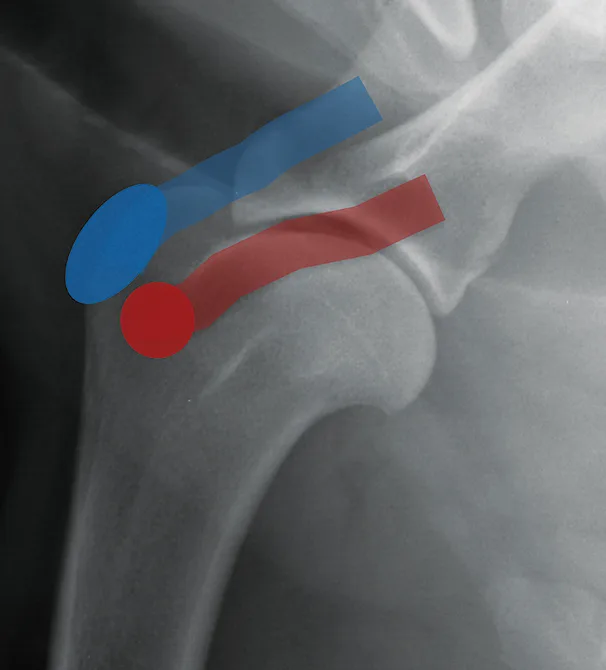

FIGURE 2

Lateral radiograph of a normal shoulder showing the supraspinatus insertion (blue oval) and tendon course (blue bar) as well as the infraspinatus insertion (red circle) and tendon course (red bar)

The supraspinatus tendon is a broad tendon that arises from the supraspinatus muscle and is attached to the lateral aspect of the greater tubercle. Tendinopathy of this tendon is common and manifests radiographically as mineralization within the tendon, typically slightly cranial to the greater tubercle. The infraspinatus tendon is affected less commonly. This tendon arises from the infraspinatus muscle and attaches on the lateral greater tubercle, slightly distolateral to the supraspinatus tendon, and runs in an oblique plane in a caudoproximal-to-craniodistal direction (Figure 2).1